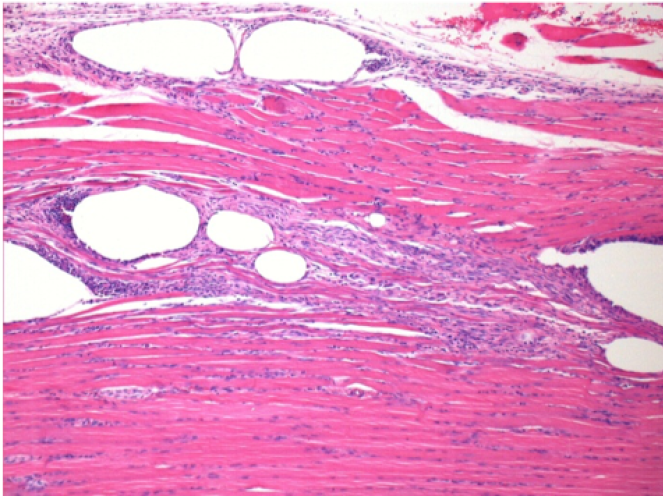

10 giorni dopo iniezione di Endopeel

Scatola Nr 2

- 10 giorni dopo iniezione 0.1ml di Endopeel nel muscolo pretibiale destro (Dx).

- Si osserva formazioni di vacuole , le quali circondate da linfociti.

- Le quali Vacuole sono differenti dal tessuto necrotico.

- La presenza di linfociti é correlata alla permeabilità delle membrane cellulari.

Sx : Controllo-100x-Giorno10

Dx:100x-Giorno10

Dx :200x-Giorno10

Dx :400x - Giorno10